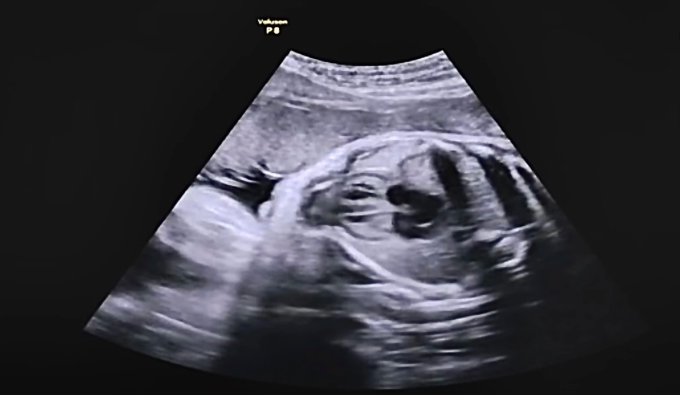

Theo TS.BS.CK2 Trà Anh Duy, Trung tâm Sức khỏe Nam giới Men’s Health, khả năng thụ thai tự nhiên không chỉ phụ thuộc vào việc tinh trùng và trứng gặp nhau, mà còn ở thời điểm chúng gặp nhau. Trong y học sinh sản, các chuyên gia gọi giai đoạn thuận lợi nhất này là "cửa sổ vàng" thụ thai. Việc hiểu rõ và tận dụng chính xác "cửa sổ vàng" giúp các cặp đôi tăng cơ hội mang thai, đồng thời giảm áp lực tâm lý, tiết kiệm thời gian và chi phí so với những phương pháp hỗ trợ sinh sản phức tạp.

"Cửa sổ vàng" thụ thai là khoảng thời gian khoảng 5-6 ngày trong chu kỳ kinh nguyệt của người nữ, kết thúc vào ngày rụng trứng. Lý do giai đoạn này được xem là tối ưu là vì thời gian sống của tinh trùng và trứng rất khác nhau: trứng chỉ tồn tại được 12-24 giờ sau khi rụng, trong khi tinh trùng khỏe mạnh có thể sống từ 3-5 ngày trong đường sinh dục nữ.

Nếu cặp đôi quan hệ vào 1-2 ngày trước khi trứng rụng, tinh trùng sẽ "chờ sẵn" tại vòi trứng để thụ tinh ngay khi trứng được phóng thích. Đây chính là nguyên nhân khiến các nghiên cứu cho thấy tỉ lệ thụ thai cao nhất thường rơi vào giai đoạn này.